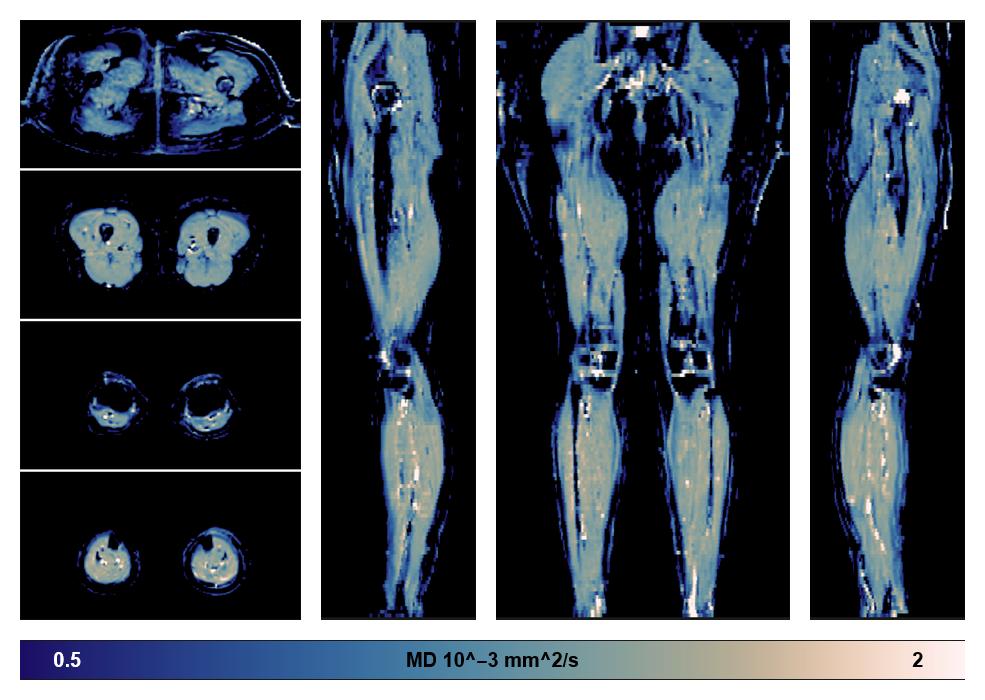

• Mean diffusivity

IVIM corrected whole leg muscle mean diffusivity obtained from diffusion tensor imaging.